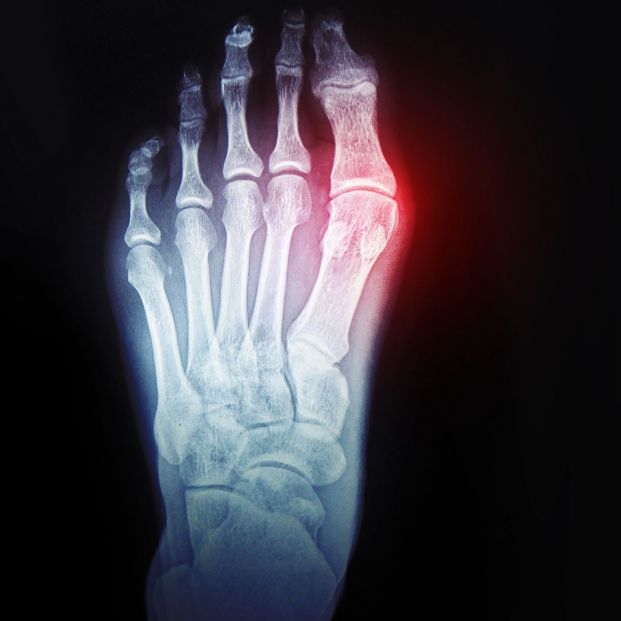

Si una vez pasado este tiempo (se podrá tomar algún analgésico antiinflamatorio), el dolor no solo persiste, sino que se hace más incómodo, habrá que acudir al médico para que lleva a cabo las pruebas necesarias. Estas suelen ser radiografías, aunque si es necesario un mayor detalle, la prueba deberá ser una resonancia magnética. A eso le unirá una exploración de la zona.

En el caso de que la fractura sea grave y difícil de curar con reposo e inmovilización, podría recurrirse a la cirugía. “En algunos casos, es posible que el cirujano ortopédico necesite utilizar pernos, placas o tornillos para mantener la posición adecuada de los huesos durante la consolidación. Estos materiales pueden extraerse una vez que la fractura se haya curado si provocan dolor o sobresalen”, explican en la citada clínica al respecto.

Sin embargo, la cirugía suele ser el último recurso, optando generalmente por tratamientos menos invasivos. Uno de ellos es la reducción, que consiste en que el especialista tenga que mover los huesos desplazados por la fractura (si es completa) para que vuelvan a alinearse. Este procedimiento es bastante doloroso, con lo que el paciente suele estar sedado o haber tomado algún relajante que minimice el dolor.

Una vez realizada la reducción, se realiza la inmovilización de la zona, la cual suele realizarse con la colocación de una escayola. Por supuesto, no es necesaria la anterior colocación para poner los yesos. Si los huesos están en el lugar que les corresponde, también de inmovilizará el área.